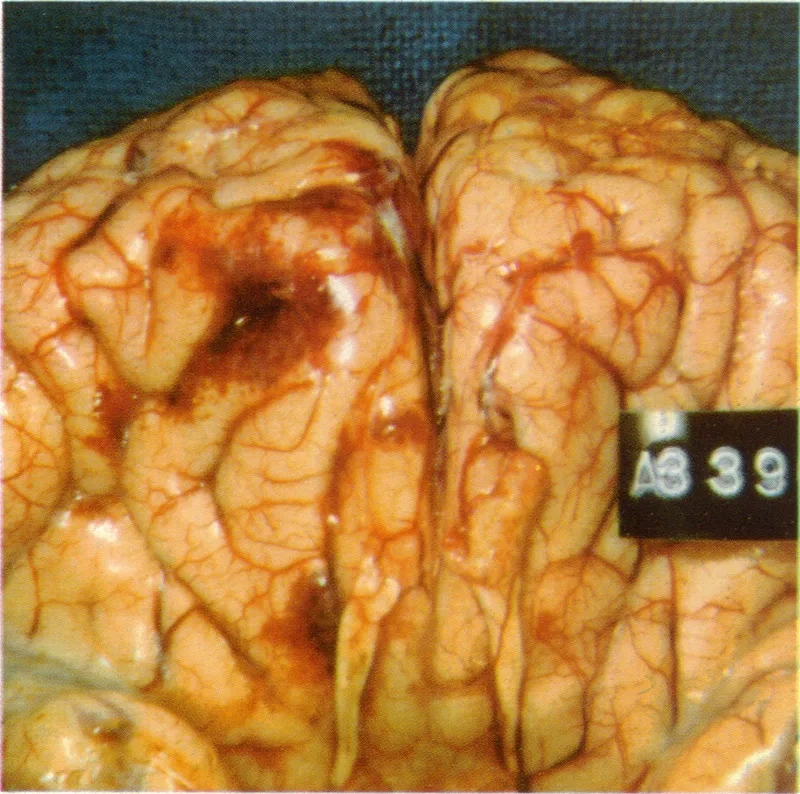

Image of the disease Primary Amebic Meningoencephalitis